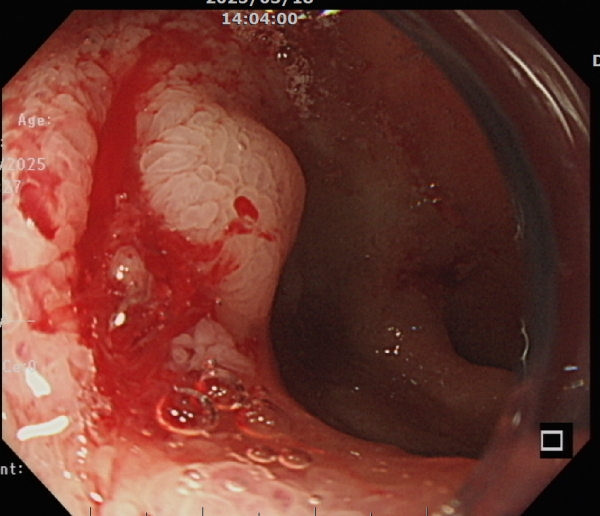

檢查時,食道與胃部乾乾淨淨,完全沒有血跡。但就在下一秒,鮮紅的血從幽門湧入胃內,立刻通過幽門進入十二指腸,發現裡面一片血紅。此時,先前在胃鏡前端裝上的透明帽發揮了關鍵作用,它能幫助推開腸道黏膜、沖水清理,讓視野更清楚。在仔細搜尋後,在十二指腸第一部位發現出血區域,但由於出血速度太快,無法立即看到破裂的血管。

首先,局部注射腎上腺素(epinephrine),幫助暫時收縮血管、減緩出血。終於能清楚看見一個潰瘍,中央露出一條血管,隨即將潰瘍與血管使用止血夾,確保不再出血。經過醫療程序的處置,病人順利住院,血色素逐漸回升,黑便狀況也獲得改善。

看見潰瘍的地方,中央露出一條血管,先處理減緩出血。(手術示意圖/北榮新竹分院 提供)